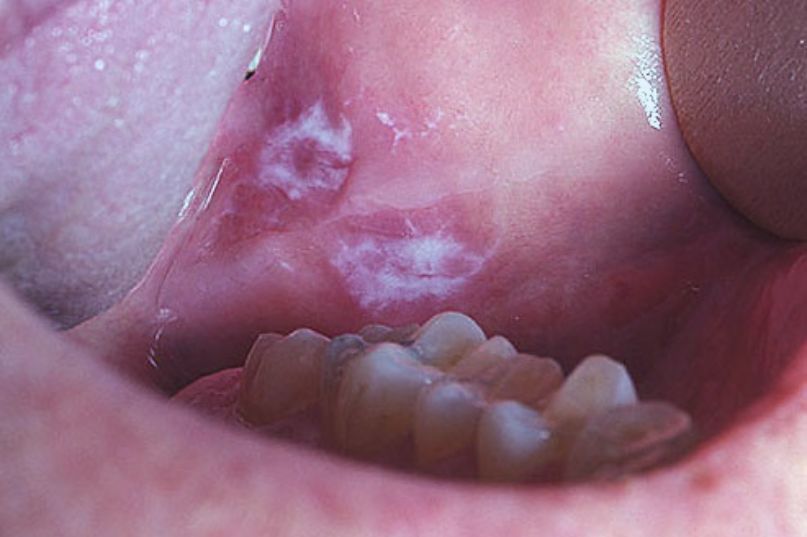

Causes and Symptoms of Mouth Cancer

While mouth cancer can affect anyone, it is mostly associated with age and gender. Even so, an overwhelming percentage (91%) of mouth cancers are strongly linked to lifestyle. This means that many cases can be prevented. To learn more about the risk factors connected to mouth cancer, continue reading below.